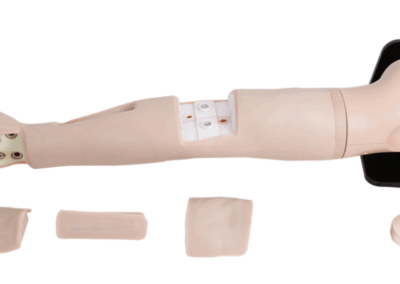

Simuladores de Habilidades Clínicas

Treinamento prático em procedimentos médicos essenciais.